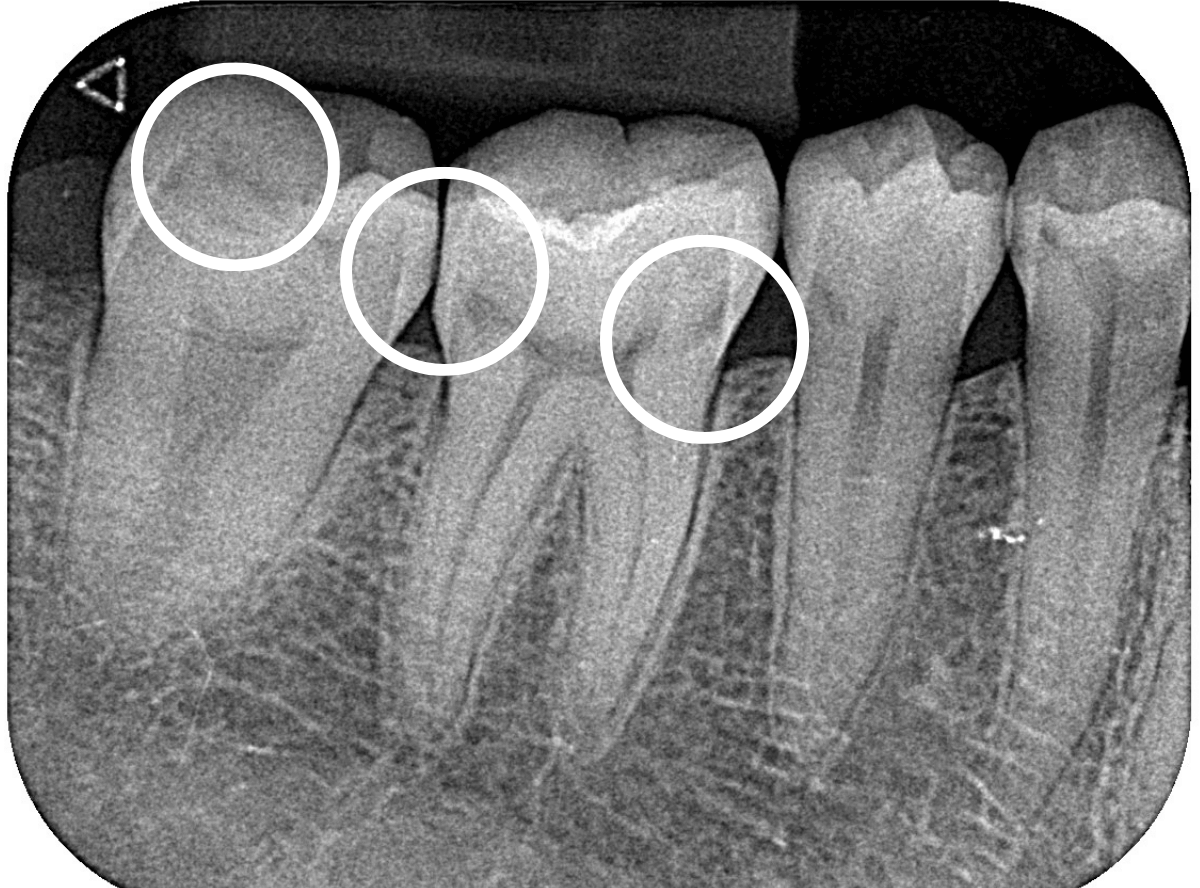

レントゲン写真を撮影しました。

青い線が神経

黄色い線がレジン

赤い線が虫歯

です。

思ったよりも深い虫歯をレジンで埋めてあったようで、さらにその中が虫歯になっている状況です。

神経までかなり近い虫歯と思われます。

症状はありません。